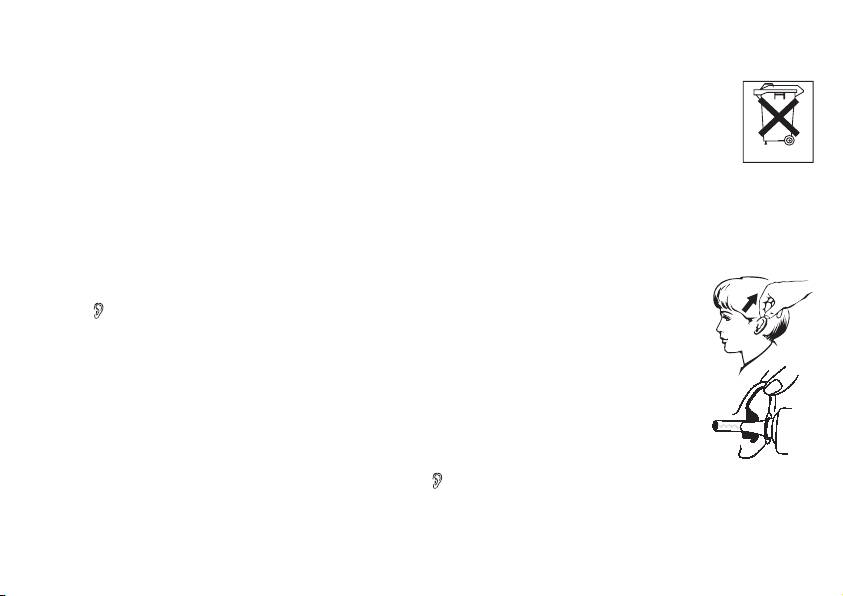

6.1 Misurazione nell‘orecchio

Dopo un breve autotest e due brevi bip il termometro è pronto per la misurazione della temperatura

nell’orecchio. Il termometro a infrarossi si trova in modalità “Termometro da orecchio” indicata anche

dall’icona

.

Dato che il condotto uditivo è leggermente curvo, tirare delicatamente indietro e verso l’alto l’orecchio

prima di inserire la punta del sensore.

Questa operazione è particolarmente importante per orientare la punta del sensore direttamente verso il

timpano. Inserire la punta del sensore con precauzione e premere il tasto di misurazione „SCAN“ per circa

1 secondo.

La ne della misurazione viene segnalata da un lungo bip. Rilasciare il tasto “SCAN”. Si può leggere ora

il valore misurato. Inoltre si accende il LED in funzione del risultato della misurazione: il LED verde indica

che la temperatura corporea si trova nel campo normale, il LED rosso si accende invece quando la tempe-

ratura supera 37,5 °C, ossia allarme febbre.

Il termometro segnala con due brevi bip e l’icona dell’orecchio

non più lampeggiante, che l’apparecchio è pronto per

effettuare una nuova misurazione.